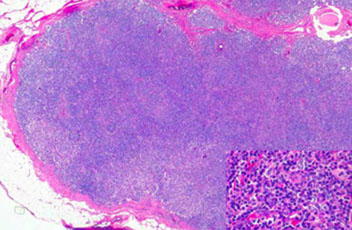

Reactive Follicular Hyperplasia (RFH). Follicles (B-cell compartment) have varying size and are well spaced from one another. There is a nice capsule and subcapsular sinus. In medullary compartment where plasma cells and memory B-cell live, the sinuses are open and patent. Note the relative abundance of the paracortex compared to the cortex, which is an important feature for B9 LNs.

Hyperplastic lymphoid follicle. Germinal center with sharply demarcated mantle zone (solid blue arrow). Dark zone of GC with starry-sky pattern (open blue arrow) and light zone (open black arrow) with small centrocyte predominance [2]